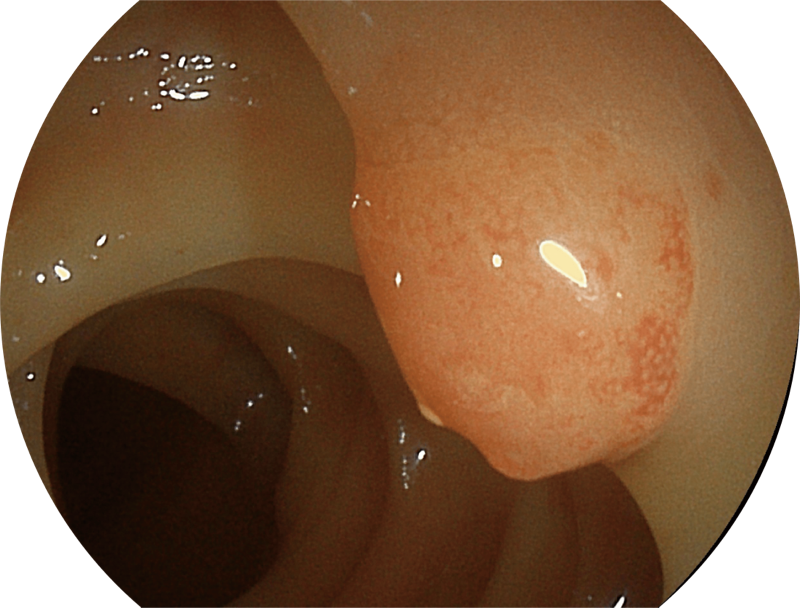

能够凸显黏膜浅层和中层血管轮廓,适用于中、远景观察下的病灶识别和早癌筛查。

SFI图像